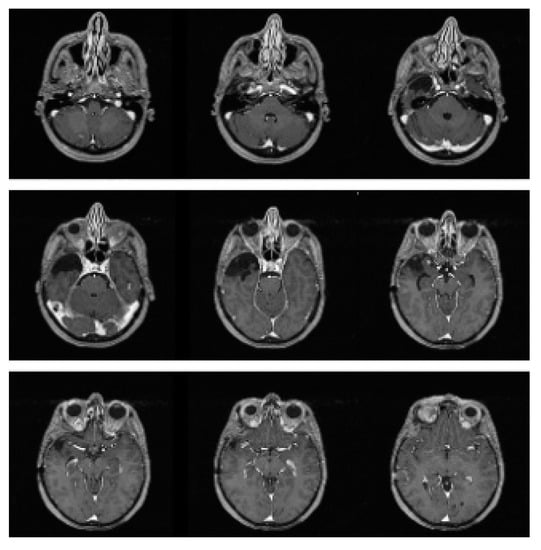

2. Case Presentation